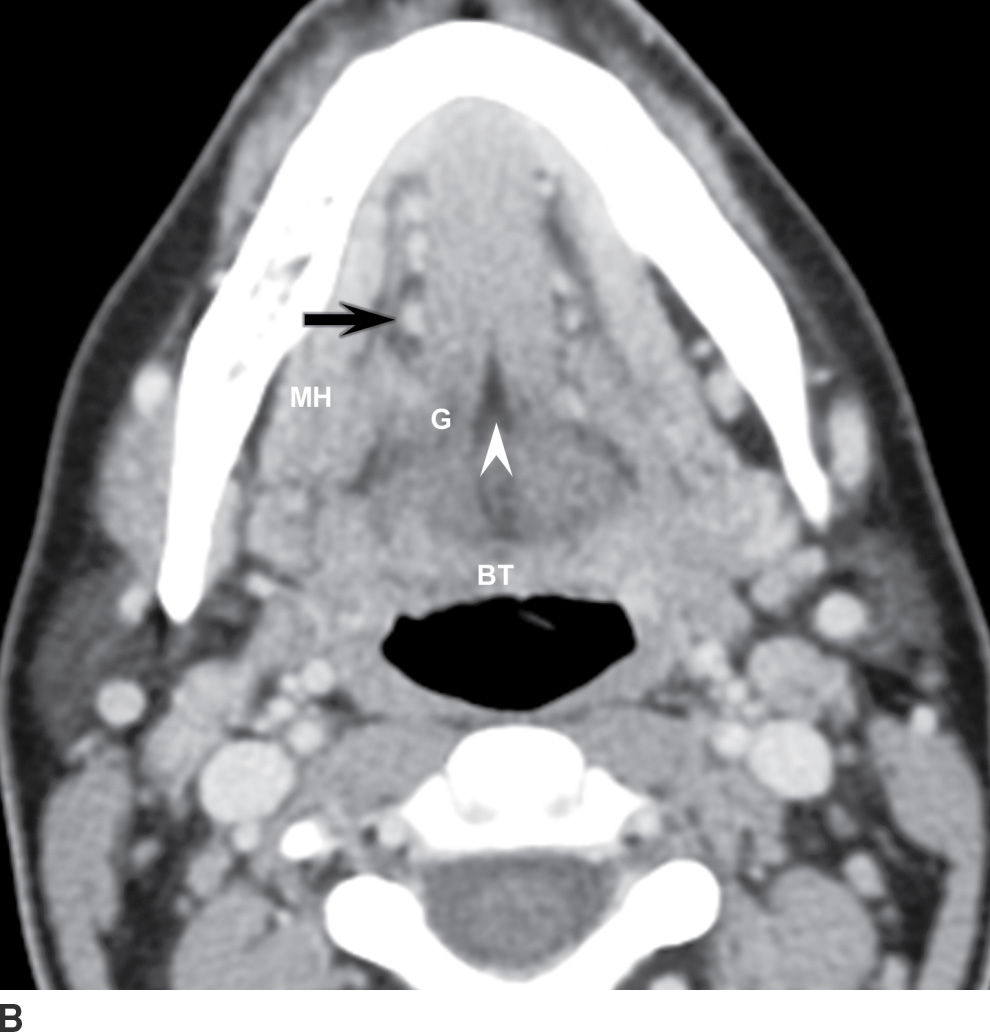

From radiologykey.com

Mucosal Cancers Neck Primaries and the Lymph Nodes Radiology Key Spine Cancer Neck Learning that you have a spinal tumor can be overwhelming. Some of the cancers that may involve the spine. Spinal metastasis (metastatic spinal cancer) happens when cancer in another part of your body spreads ( metastasizes) to. S pinal tumors can involve the neck, back and lower back. A spinal tumor is an abnormal growth of cells within or surrounding. Spine Cancer Neck.

Mucosal Cancers Neck Primaries and the Lymph Nodes Radiology Key Spine Cancer Neck A spinal cord tumor, also called an intradural tumor, is a spinal tumor that that begins within the spinal cord or the covering of the spinal cord (dura). Learning that you have a spinal tumor can be overwhelming. But you can take steps to cope after your diagnosis. A spinal tumor is an abnormal growth of cells within or surrounding. Spine Cancer Neck.

Mucosal Cancers Neck Primaries and the Lymph Nodes Radiology Key Spine Cancer Neck Most spinal cancer occurs inside the spinal column and usually doesn’t affect the spinal cord. A spinal cord tumor, also called an intradural tumor, is a spinal tumor that that begins within the spinal cord or the covering of the spinal cord (dura). Learning that you have a spinal tumor can be overwhelming. Some of the cancers that may involve. Spine Cancer Neck.